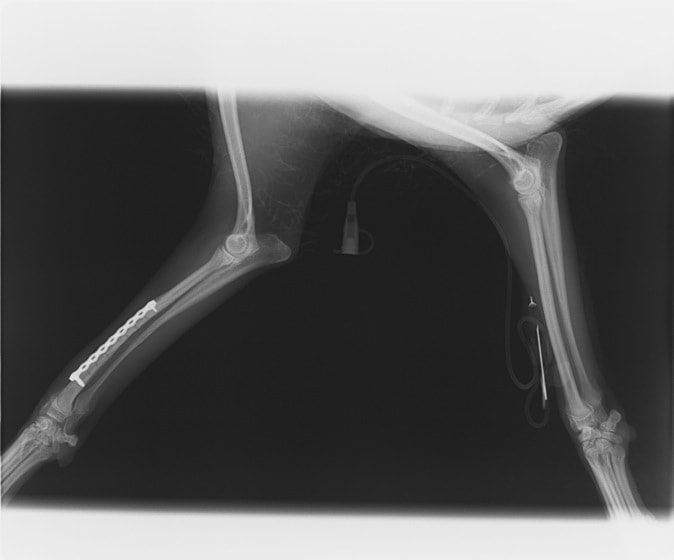

症例3:キルシュナーワイヤーのピンニングによる整復

ペルシャ猫 11ヶ月齢 雄

他院にて左大腿骨遠位の成長板骨折(salter-harrisⅠ型)が認められており、治療相談を目的として来院。当院にて、キルシュナーワイヤーを用いたピンニングにより骨折部位の整復を行いました。術後の経過は良好で、現在も経過観察中です。

術前レントゲン

術後レントゲン

Arthrex社のターゲティングデバイスを用いてピンニングの位置を調整することで、確実な固定を行っています。当院ではこの手術器具以外にも、人の手術にも使用される様々な器具を導入し、手術精度を高め、また医療メーカーと新しい器具の開発、試作にも取り組んでおります。